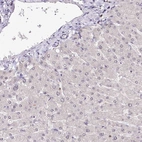

Immunohistochemistry analysis in human lymph node and liver tissues using Anti-POLA2 antibody. Corresponding POLA2 RNA-seq data are presented for the same tissues.